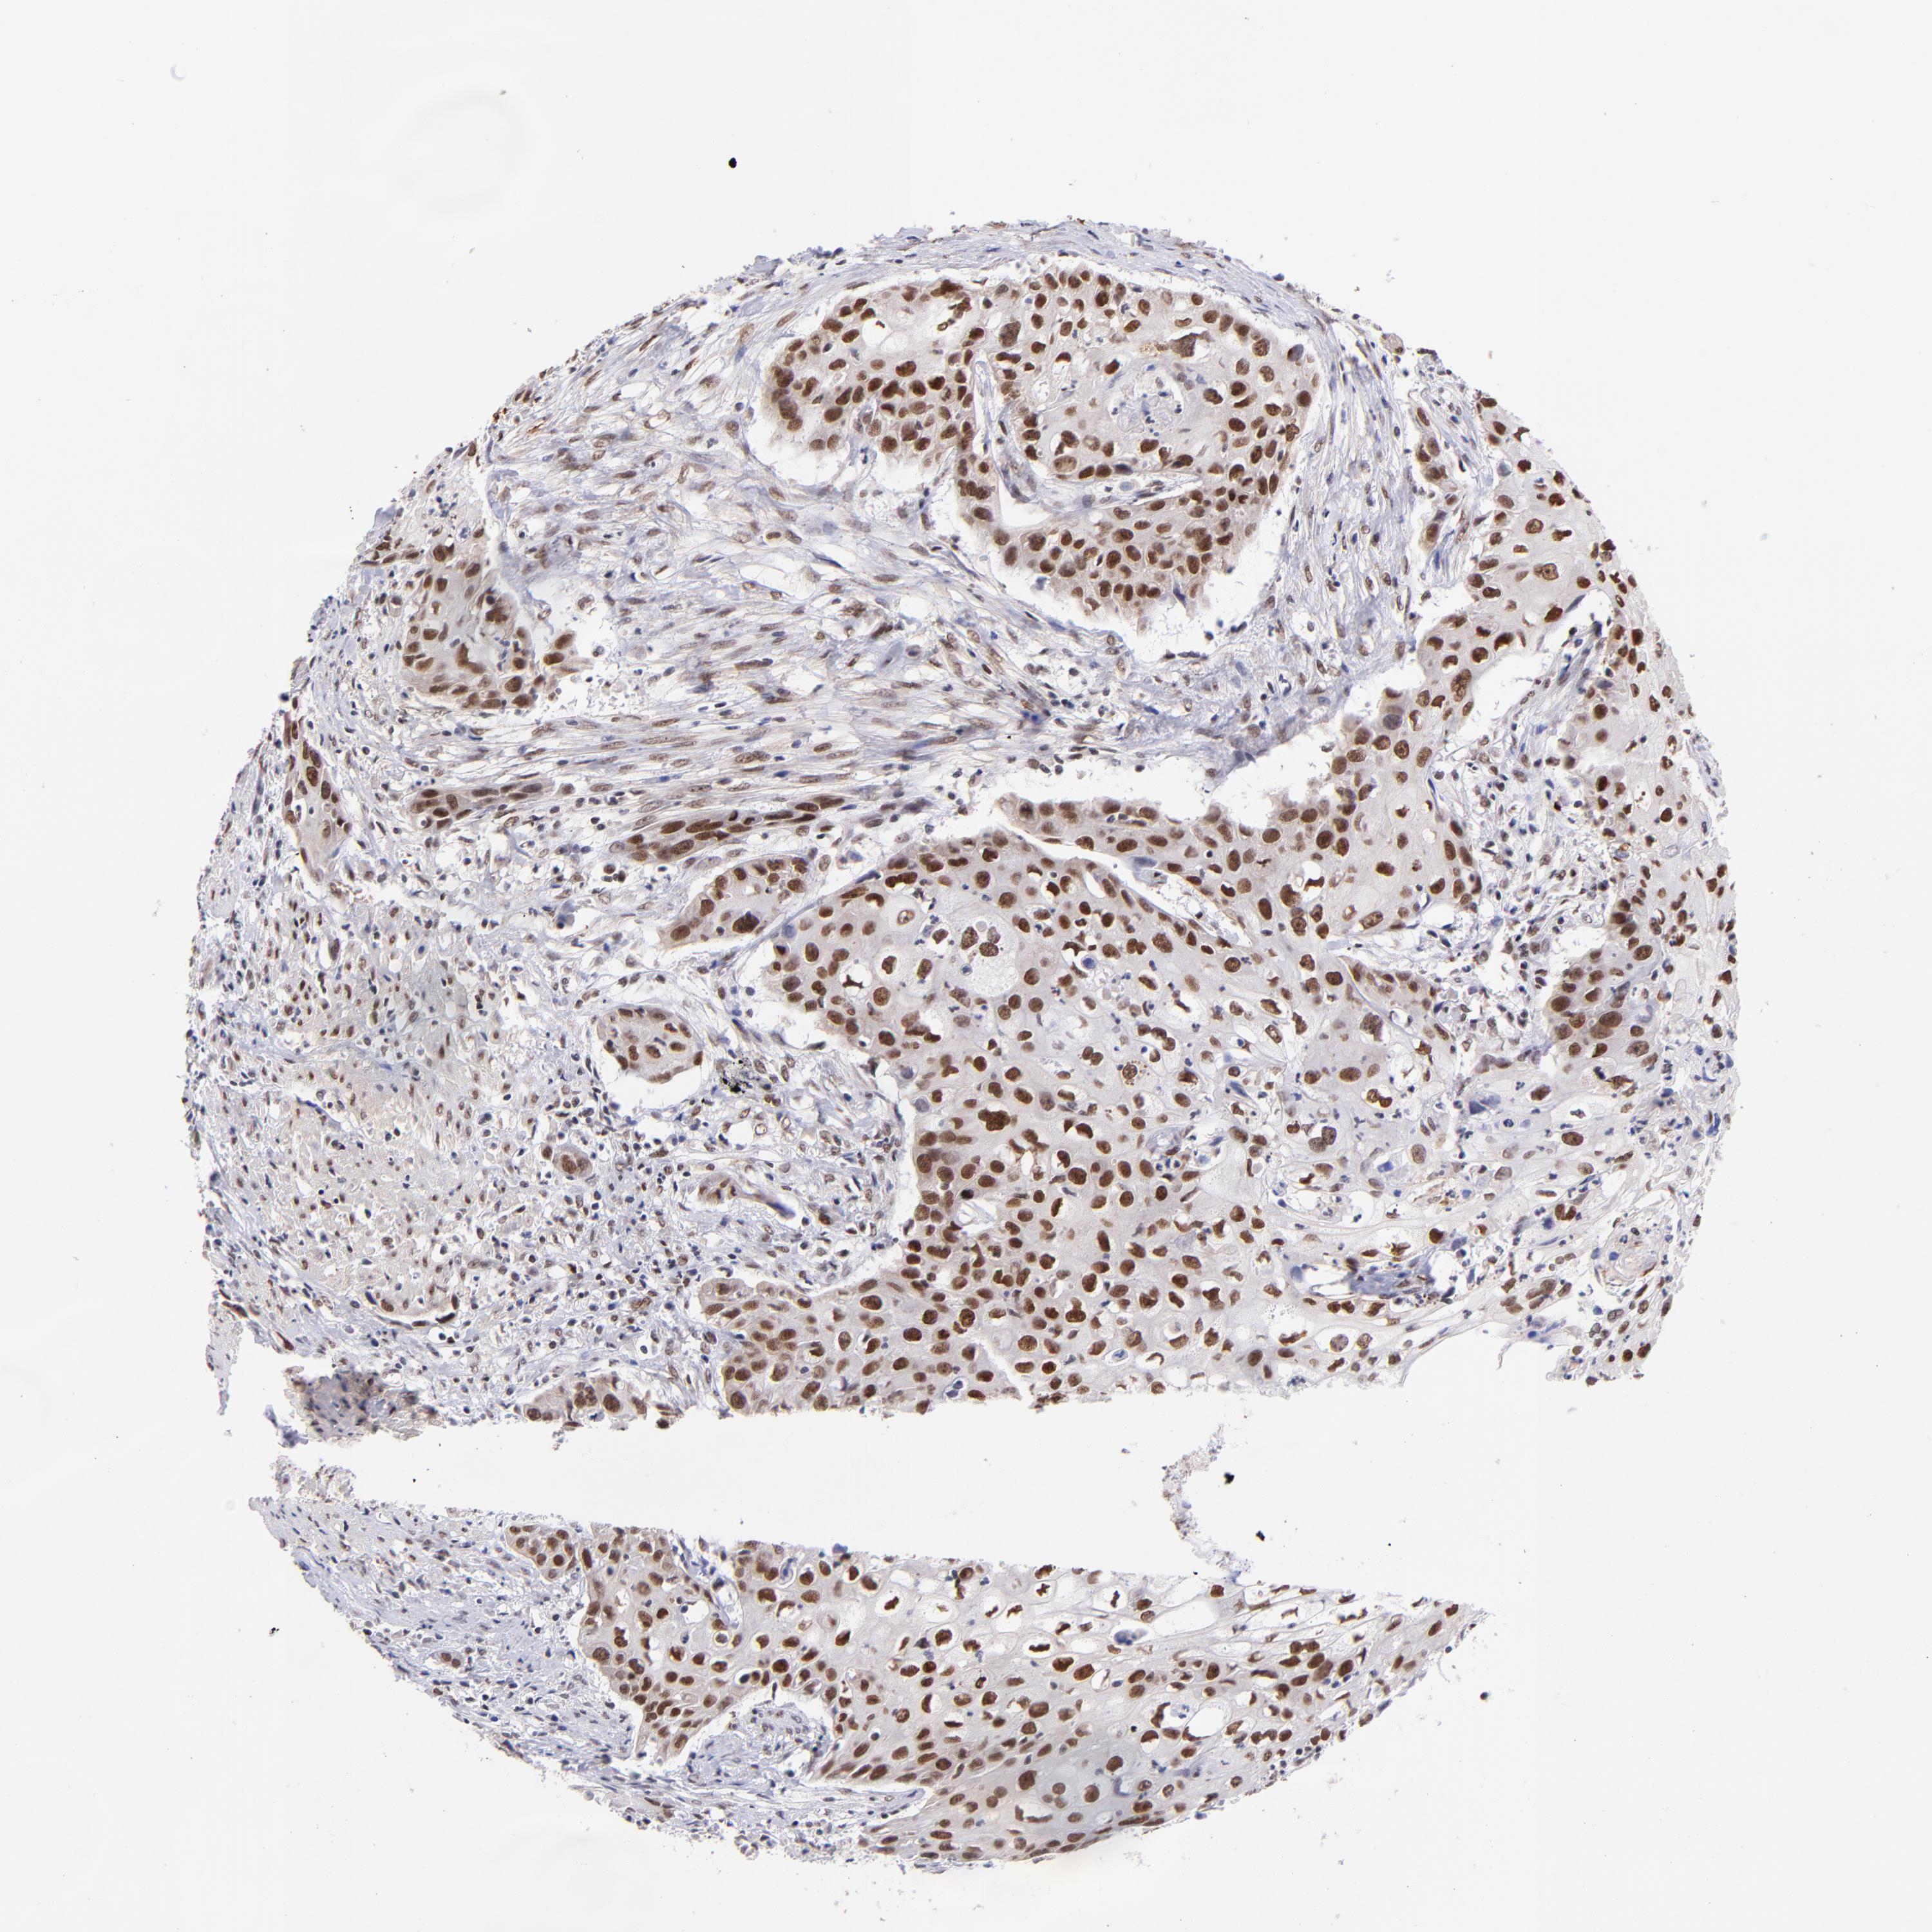

UROTHELIAL CANCER - Protein expressioni

A mouse-over function shows sample information and annotation data. Click on an image to view it in a full screen mode. Samples can be filtered based on level of antibody staining by selecting one or several of the following categories: high, medium, low and not detected. The assay and annotation is described here.

Note that samples used for immunohistochemistry by the Human Protein Atlas do not correspond to samples in the TCGA dataset.

Antibody stainingi

Antibody staining in the annotated cell types in the current human tissue is reported as not detected, low, medium, or high, based on conventional immunohistochemistry profiling in selected tissues. This score is based on the combination of the staining intensity and fraction of stained cells.

Each image is clickable and will lead to virtual microscopy that enables deeper exploration of all samples and also displays staining intensity scores, fraction scores and subcellular localization as well as patient and tissue information for each sample.

Antibody HPA003111

Staining

High

Medium

Low

Not detected

Intensity

Strong

Moderate

Weak

Negative

Quantity

>75%

75%-25%

<25%

None

Location

Nuclear

Cytoplasmic/membranous

Cytoplasmic/membranous,nuclear

Urothelial carcinoma, High grade

Urothelial carcinoma, Low grade